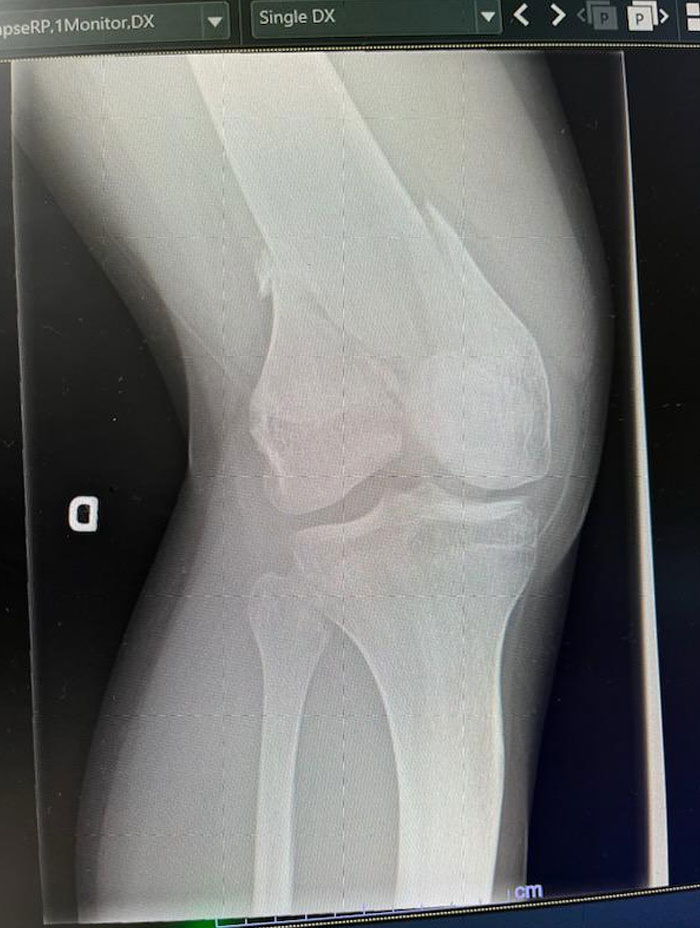

Radiologist Said There Was No Broken Bone.. I’m Skeptical

Broke Some Bones A While Back

Omg I snapped my femur clear in half years ago; my thigh was bent! The only thing saving it from being a compound fracture was the tight jeans I was horseback riding in. THIS HURTS TO LOOK AT!!!